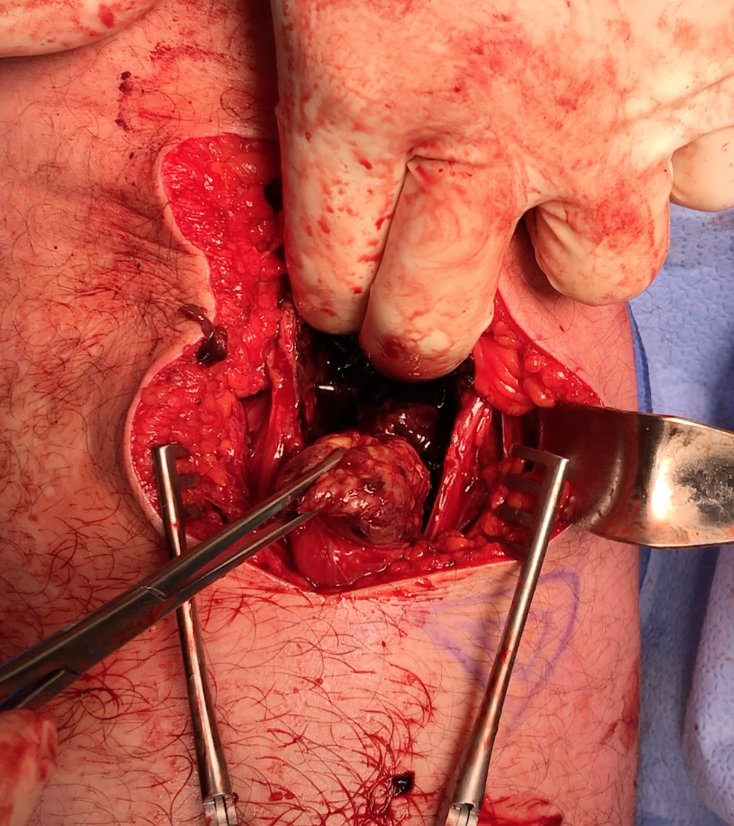

Hamstring (*) with sciatic nerve lateral to hamstring (blue vessiloop)

Identify and release proximal hamstring tendon

Stump of the conjoint tendon (*)

Sciatic nerve with blue vessiloops